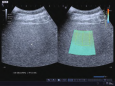

什么是声衰减成像技术?

您是否曾经在黑暗的房间打开手电筒,发现光线穿透某些材料(如玻璃)很容易,而穿过另一些材料(如木板)时亮度迅速减弱?声波在人体组织中的传播也遵循类似的原理。当我们利用超声波进行医学检查时,超声波在人体组织中传播时会出现反射、散射、衍射和被组织吸收等现象,能量随着深度的增加而逐渐减弱,且频率越高超声波衰减越严重。声衰减成像技术(atte...